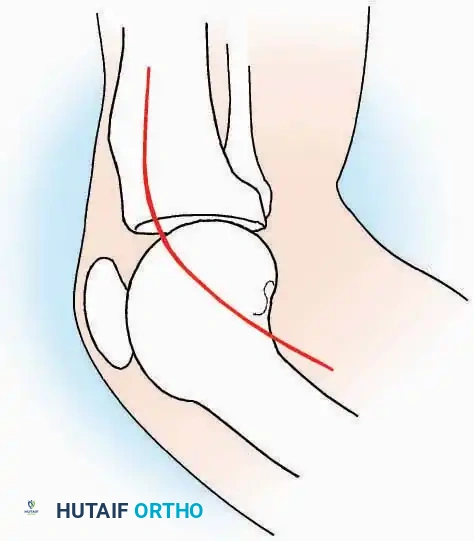

Kocher Approach (Curved L)

Indications: Complete excision of the calcaneus (calcanectomy) for malignant tumors or recalcitrant osteomyelitis.

Surgical Technique:

* Incision: Incise the skin over the medial border of the Achilles tendon, starting 7.5 cm proximal to the calcaneal tuberosity. Extend it distally to the inferoposterior aspect of the tuberosity, curve it transversely around the posterior heel, and continue distally along the lateral surface of the foot to the tuberosity of the fifth metatarsal.

* Deep Dissection: Divide the Achilles tendon directly at its insertion and carry the dissection down to the bone.

* Enucleation: To reach the superior surface, free all tissues beneath the severed Achilles tendon. The calcaneus can then be enucleated subperiosteally or extraperiosteally depending on the oncologic or infectious margins required.